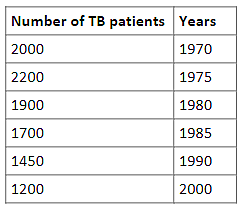

| wpSwiadI2USTefcxtGKu | Skip | No change needed | Original  |

What will be the number of TB patients in the Rosemary Hospital in the year $2030$?

Give your answer to the nearest whole number.

|

No changes |

Rationale: The question and image contain no Australian-specific spelling, terminology, units, or cultural references. The data table uses universal year formats and numerical counts of patients. The hospital name 'Rosemary Hospital' is generic. |

| wcWE4icg6snhCWls7Vla | Skip | No change needed | Original  |